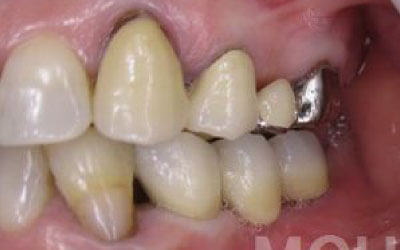

ブリッジとインプラントでは、周りの歯の寿命に大きな違いがあります。ブリッジは支えとなる歯を健康でもかなり削らなければならず、さらに噛む力が約1.5倍かかるため、その歯の寿命が短くなってしまいます。実際のデータでは、ブリッジの支えとなった歯の68%が10年以内に抜歯に至っています。

ブリッジ治療の場合も、失った歯にかかっていた力を前後の歯が支えるため、結果として残っている歯には、通常の1.5〜2倍ほどの負荷がかかってしまいます。

ブリッジなどの治療では、前後の歯を大きく削らなければならず、場合によっては虫歯でなくても神経を抜くことがあります。神経を抜いて被せ物をすると、その歯は一気に寿命の終わりに近づいてしまうのです。